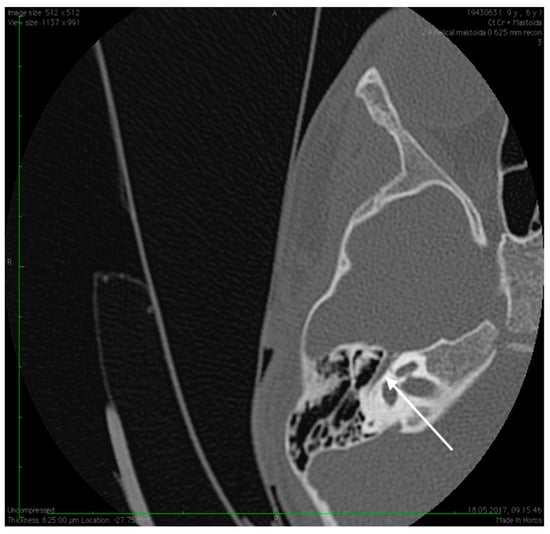

Figure 5.

High resolution axial CT scan of right temporal bone exposing the missing foramen spinosum (arrow).

Preoperative CT imaging of middle ear surgery patients is mandatory and careful interpretation of the results can sometimes prevent accidental injuries brought to a PSA. The usual findings are a small, abnormal, canaliculus leaving the carotid canal or the facial nerve, a straight line structure crossing over the promontory, an unusual widening of the fallopian canal or a different canal parallel to it between the geniculate and the oval window niche and absence of the foramen spinosum []. Our CT findings coincide with some of the aforementioned signs, as there can be seen no trace of the foramen spinosum in the affected ear (Figure 5), in contrast to the contralateral ear (Figure 3). There is also a widening of the facial nerve canal that can be observed in Figure 4. It came as no surprise that the stapes could not be described in the CT images, as the literature review acknowledges the possible stapes malformations that come along with PSA.